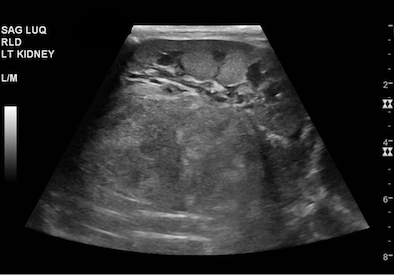

All’arrivo in PSP la lattante appare in discrete condizioni generali, reattiva alle stimolazioni ma con tendenza ad assopirsi per poi risvegliarsi improvvisamente in pianto. In triage si evidenziavano tachicardia (FC 180- 200 bpm) e polipnea (FR 60 apm) in apiressia. Considerata l’ipotesi diagnostica di invio, si valutano immediatamente le pressioni e le saturazioni d’ossigeno ai quattro arti, che sono concordi. Tuttavia, si riscontra ipertensione severa, con valori ampiamente al di sopra del 95 centile per età (PAS 150-180 mmHg, PAD 120-160 mmHg). Alla visita la piccola è pallida, con mucose asciutte e fontanella depressa; al torace si ausculta un soffio sistolico e i polsi femorali sono isosfigmici; palpando l’addome si apprezza una massa addominale che si estende dall’ipocondrio destro alla fossa iliaca ipsilaterale. L’ecografia addominale eseguita in urgenza dimostra una voluminosa massa addominale che comprime e disloca il rene di destra, sospetta per neuroblastoma (Figura).